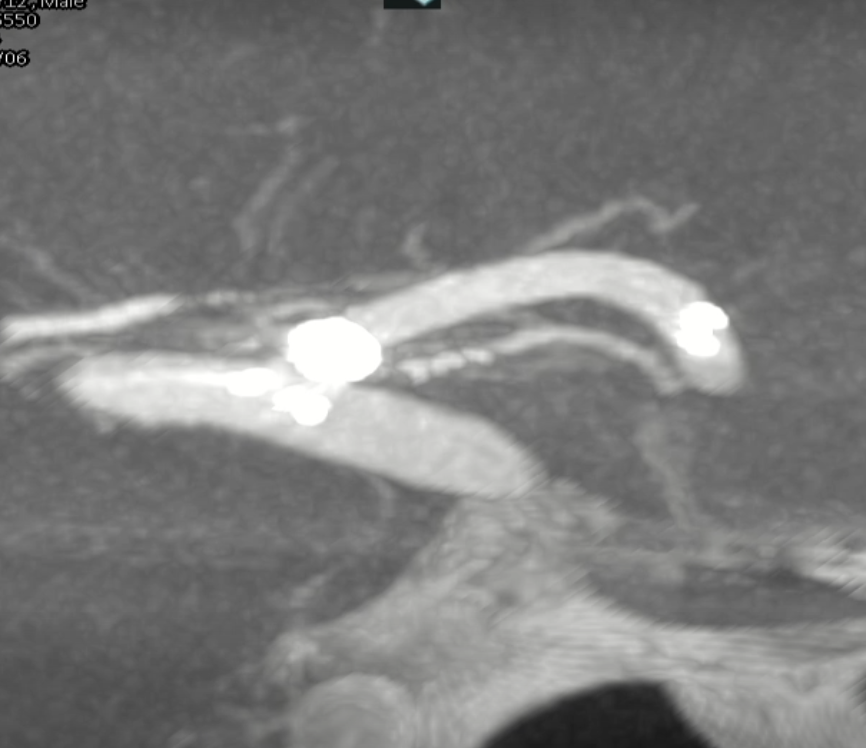

术后正侧位造影:Raymond Ⅲ级

术后支架重建:支架打开良好,近端Marker位于颈内动脉分叉处

继续填入Target 1.5/2弹簧圈成篮,后完全释放支架,其近端位于颈内动脉分叉处,远端位于A1远端。

通过调整栓塞微导管的张力继续填入Target 1/3弹簧圈。